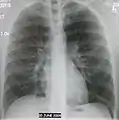

AP CXR showing right lower lobe pneumonia